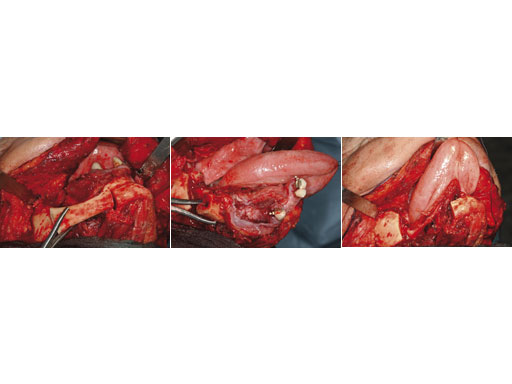

Case 1: A 27-year-old woman with an odontogenic myxoma in the left mandible. The preformed reconstruction plate was inserted prior to the tumor resection using a transoral approach with only a small additional transbuccal incision. To date the patient is free of symptoms with no signs of hypoaesthesia of the mandible and no signs of relapse. After another relapse-free period dental implants are planned for oral rehabilitation.

Fig 1 ad Transoral application of preformed reconstruction plate before tumor dissection.

Fig 3ac En bloc resection of the mandible body segment with the overlying soft tissues of the floor of the mouth.